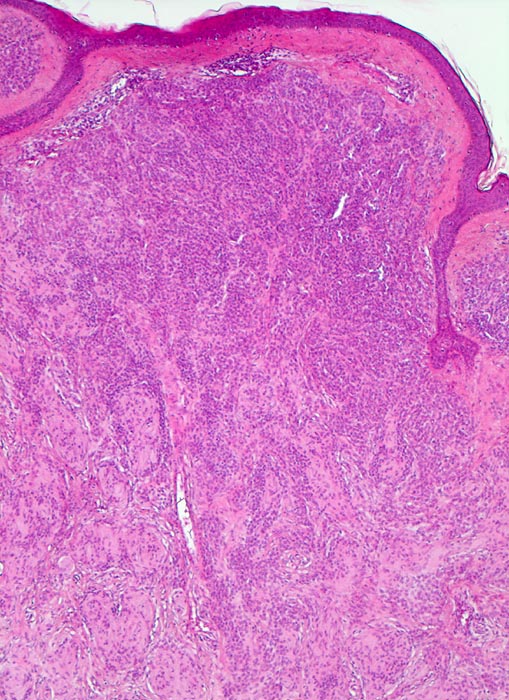

PathoPic – image database / PathoPic ID 3576 - dermaler Naevuszellnaevus

dermaler Naevuszellnaevus

benigner Tumor

Haut, Rumpf

Unauffällige Epidermis. Zwischen den Naevuszellen und der Epidermis schmale Schicht von zellarmem Bindegewebe. Ein dichtes Infiltrat von Naevuszellen füllt das Corium aus. Zwischen den Naevuszellen vereinzelte Spaltbildungen (typischer Fixationsartefakt).

Graubraune, leicht erhabene, scharf begrenzte Hautveränderung über dem Schulterblatt.

Histologie

50